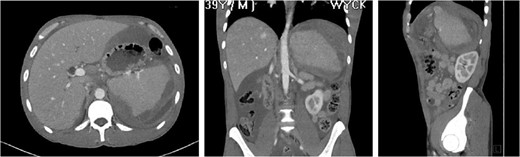

Splenic rupture is a rare but serious complication from cocaine abuse. Given the ubiquitous prevalence of abuse and the potential for death from intraperitoneal bleeding, the prompt diagnosis and treatment of cocaine-induced disease including splenic rupture is essential. The management for splenic rupture from traumatic and atraumatic etiology has shifted from emergent laparotomy and splenectomy to non-operative approach with transcatheter splenic artery embolization. We report a 39-year-old male with a significant substance abuse history who presented with atraumatic splenic rupture. He was managed nonoperatively with adjunctive transcatheter splenic artery embolization. His post-procedure course was complicated by an intra-abdominal abscess requiring drainage via interventional radiology guided pigtail catheter placement and intravenous antibiotics. This case report is intended to raise awareness of the potentiating effects of cocaine use in this patient population and highlight questions raised during this patient's management.

CASE REPORT

The ‘Islands’ of preserved spleen lit up with IV contrast surrounded by a large collection of old blood and devitalized tissue.